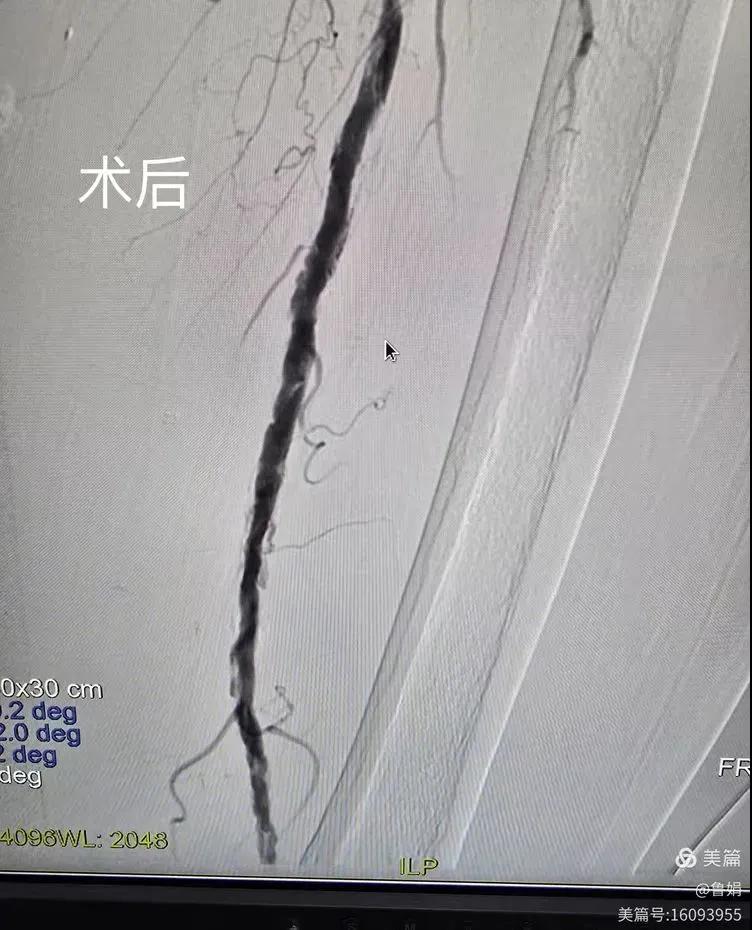

據(jù)悉,該患者,女,73歲,下肢動脈硬化閉塞癥,“以靜息痛,間歇性跛行”入院,CTA評估:股淺動脈,腘動脈間斷性多段重度狹窄,外二科血管外科團隊根據(jù)患者病情,結(jié)合檢查結(jié)果,經(jīng)過科室會診后,決定對該病人行介入治療。手術(shù)由周創(chuàng)業(yè)副主任與北大一院血管外科專家郭宏杰教授聯(lián)合開展,對股淺動脈,腘動脈重度閉塞段行血管開通+藥涂球囊擴張成形,術(shù)后狹窄明顯緩解,血流恢復!